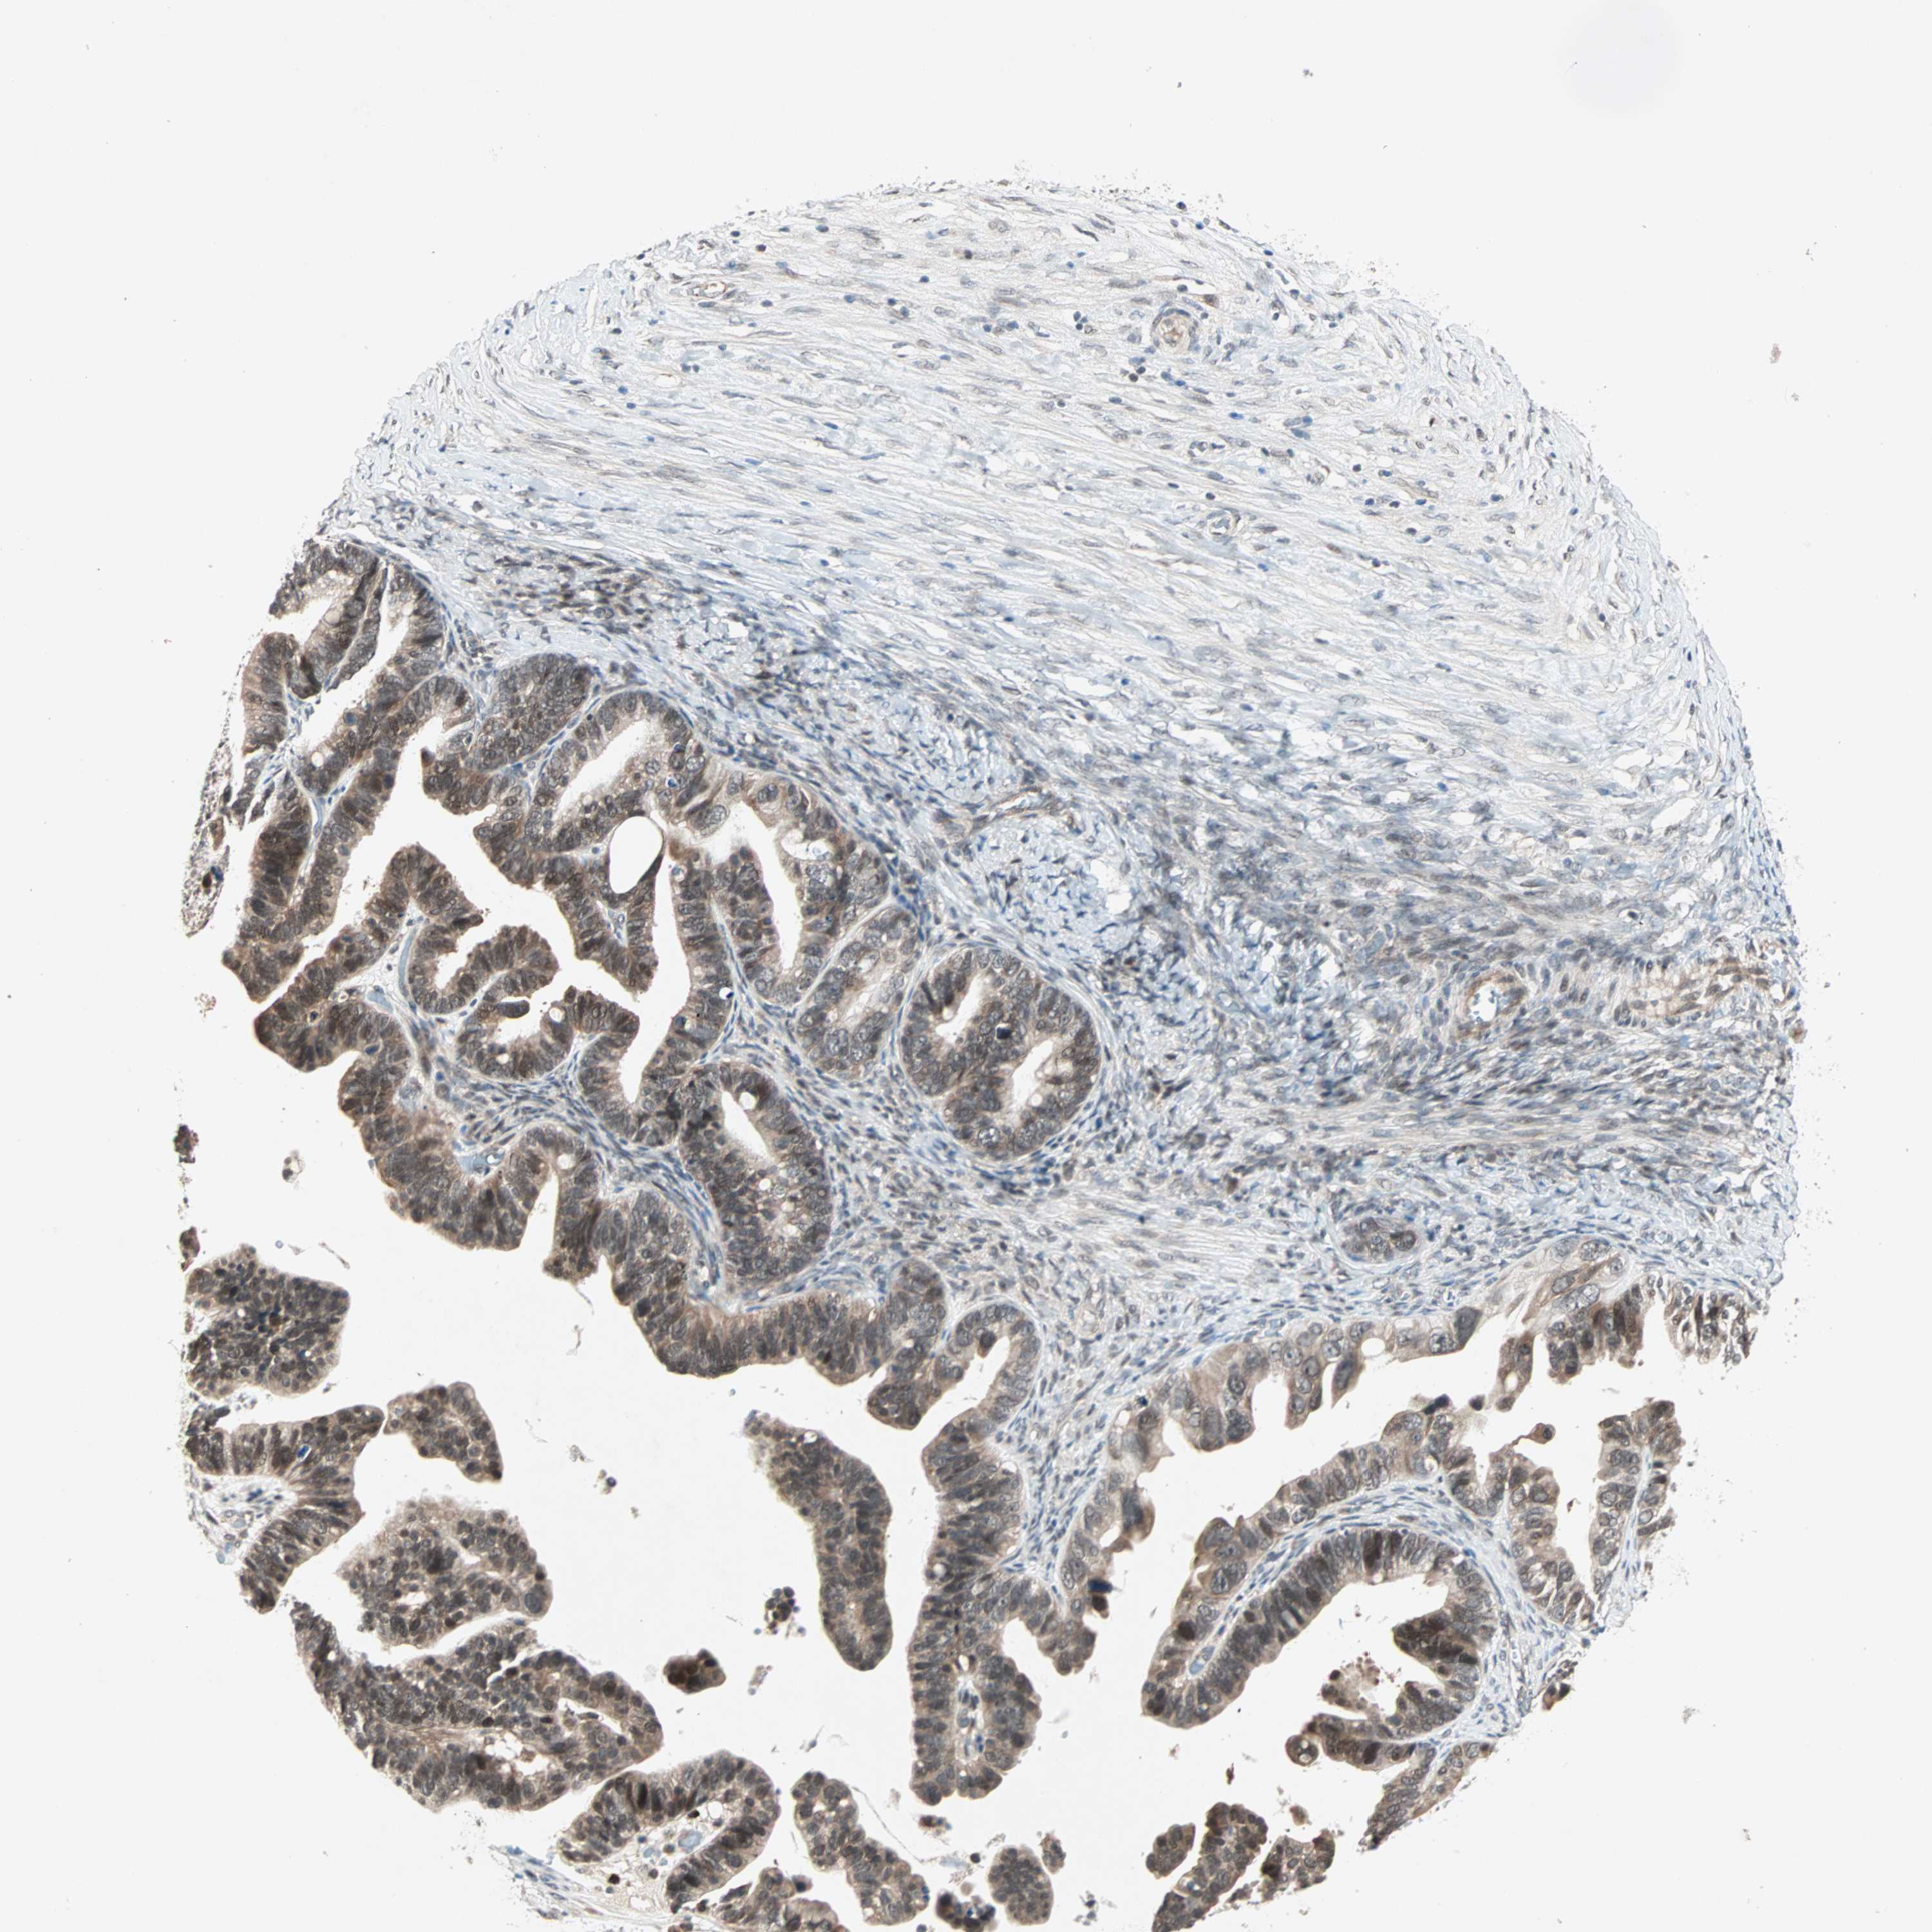

OVARIAN CANCER - Protein expressioni

A mouse-over function shows sample information and annotation data. Click on an image to view it in a full screen mode. Samples can be filtered based on level of antibody staining by selecting one or several of the following categories: high, medium, low and not detected. The assay and annotation is described here.

Note that samples used for immunohistochemistry by the Human Protein Atlas do not correspond to samples in the TCGA dataset.

Antibody stainingi

Antibody staining in the annotated cell types in the current human tissue is reported as not detected, low, medium, or high, based on conventional immunohistochemistry profiling in selected tissues. This score is based on the combination of the staining intensity and fraction of stained cells.

Each image is clickable and will lead to virtual microscopy that enables deeper exploration of all samples and also displays staining intensity scores, fraction scores and subcellular localization as well as patient and tissue information for each sample.

Antibody HPA007267

Staining

High

Medium

Low

Not detected

Intensity

Strong

Moderate

Weak

Negative

Quantity

>75%

75%-25%

<25%

None

Location

Nuclear

Cytoplasmic/membranous

Cytoplasmic/membranous,nuclear

Cystadenocarcinoma, serous, NOS

Carcinoma, endometroid

Cystadenocarcinoma, mucinous, NOS

Carcinoma, NOS